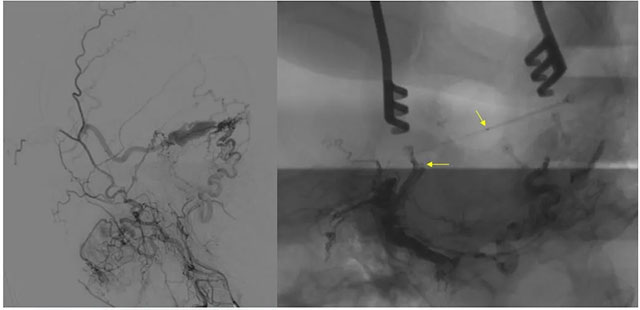

▲ 术前定位

8月23日,在复合手术室,在长海医院方亦斌教授指导下,张琪博士根据之前造影手术标记点确定平行左侧外耳道手术切口约 8cm,切开头皮各层至颅骨,剥离骨膜,牵开,以咬骨钳咬开一约 3cm 缺口,充分暴露横窦。

▲ 造影确认位置后,穿刺左侧横窦,置入 Echelon10 微导管

经左侧股动脉以单弯造影管超选至左侧颈总动脉造影明确静脉穿刺点入路,予以穿刺针穿刺成功后造影明确在位,随后 Echelon 10微导管到位横窦,填入一枚弹簧圈做塞子,造影明确位置后,缓慢注入 Onxy18胶 5毫升,铸胶弥散良好,通过静脉逆向弥散至部分供血动脉内。复查造影,见瘘口完全被栓塞,引流静脉消失,手术成功。